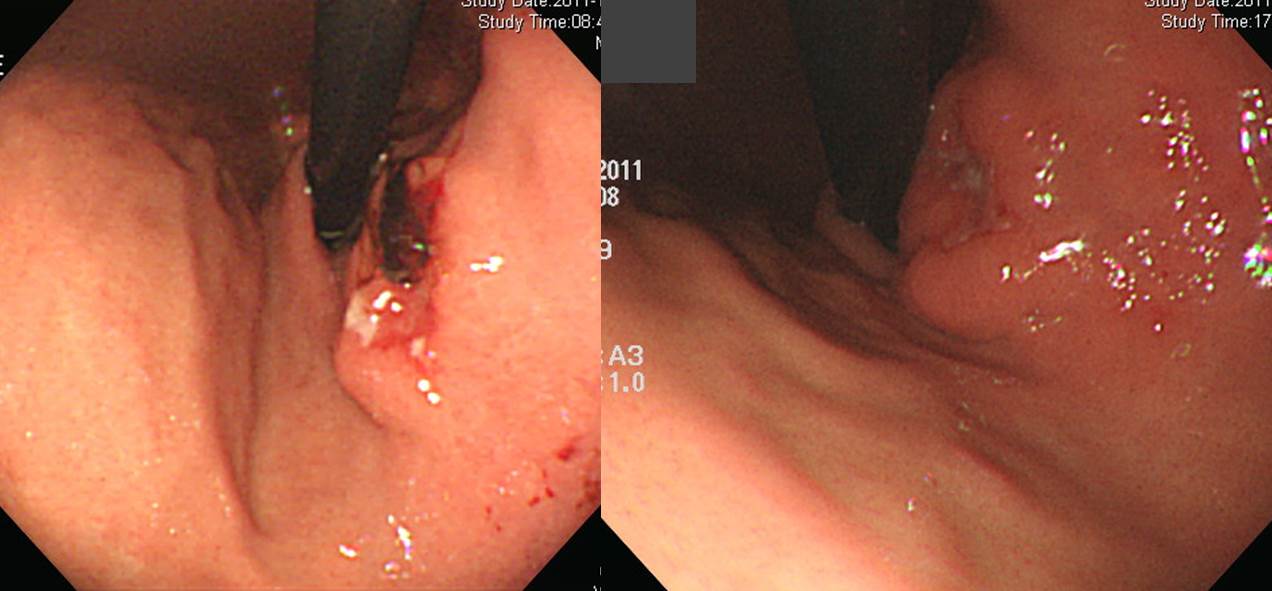

(1) Refractory ulcerÀÇ ÀÓ»ó»óÀ» º¸ÀÏ ¼ö ÀÖ½À´Ï´Ù. Á¶Á÷°Ë»çÀÇ false negative°¡ ¸¹´Ù´Â °Í°úµµ °ü·ÃµÈ Ư¼ºÀÔ´Ï´Ù. ¾Æ·¡ Áõ·Ê¸¦ º¸½Ê½Ã¿À

Refractory ulcer·Î ÀÇ·ÚµÈ ºÐÀÔ´Ï´Ù. ÀÇ·Ú ÈÄ ³»½Ã°æ Á¶Á÷°Ë»ç¿¡¼­ signet ring cell carcinoma°¡ ³ª¿Ô½À´Ï´Ù. ¼ö¼ú ÈÄ ÃÖÁ¾ º´¸®´Â carcinoma with lymphoid stroma·Î ³ª¿Ô½À´Ï´Ù. Lymphoepithelioma-like carcinoma¶ó°í ºÎ¸£´Â ŸÀÔÀÔ´Ï´Ù. Lymphoid stroma »çÀÌ¿¡ ¹ÌºÐÈ­Á¶Á÷Çü À§¾ÏÀÌ ¹ÚÇôÀÖ´Â ÇüÅÂÀ̹ǷÎ, À°¾ÈÀûÀ¸·Î´Â SMT ºñ½ÁÇÏ°Ô º¸À̰í, Á¶Á÷°Ë»çÀÇ false negative°¡ ¸¹Àº °Í °°½À´Ï´Ù.

Early gastric carcinoma

1. Location : lower third, Center at antrum and greater curvature

2. Gross type : EGC type IIc

3. Histologic type : carcinoma with lymphoid stroma

4. Histologic type by Lauren : mixed

5. Size : 3.8x1.9 cm

6. Depth of invasion : invades mucosa (muscularis mucosae) (pT1a)

7. Resection margin: free from carcinoma

8. Lymph node metastasis : no metastasis in 17 regional lymph nodes (pN0)

9. Lymphatic invasion : not identified

10. Venous invasion : not identified

11. Perineural invasion : not identified

12. AJCC stage by 8th edition: pT1a N0